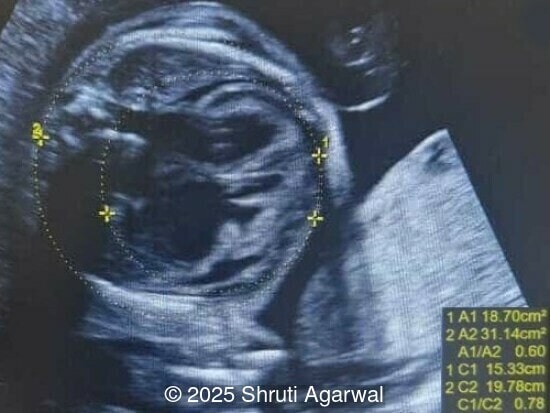

27-year-old primigravid woman presented for ultrasound evaluation at 27 weeks gestation. There was no significant family history or drug exposure during pregnancy. The following findings were observed:

We present a case of fetal anemia due to a giant chorangioma.

• Image 1,2: Large placental tumor is identified with internal vascularity

Prenatal diagnosis depends on ultrasound, however, chorangioma can cause an increase in maternal serum alpha-fetoprotein [3]. Ultrasound examination reveals a hypo- or hyperechoic, well-circumscribed mass, which is usually located underneath the chorionic plate near the umbilical cord insertion, and often protrudes into the amniotic cavity. Color Doppler demonstrates large vascular channels around and within the tumor [6,9]. In cases of giant chorangiomas, echocardiography should be performed to assess cardiac function and measure fetal middle cerebral artery peak systolic velocity for diagnosis of fetal anemia. Regular ultrasounds with Doppler studies are used to monitor tumor size, fetal growth, amniotic fluid volume, and signs of fetal anemia or heart failure. The frequency of exams is based on tumor size and associated complications. With small tumors, assessment may occur every 3-4 weeks, whereas in large tumors, the ultrasound scan may be done every 1-2 weeks [3]. These regular assessments can diagnose conditions that require intervention, such as polyhydramnios, hydrops, or hemolytic anemia.